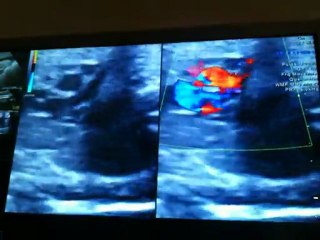

Dissection de l'aorte

Dédoublement de la paroi aortique chez un br Homme de 60 ans br Grand tabagique